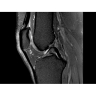

• РЧ-катушки, оптимизированные для исследования конкретных участков тела — элементы катушек высокой плотности располагаются вокруг исследуемых участков тела и при необходимости обеспечивают расширенный охват и оптимальное качество изображений при каждой процедуре.

МР-томограф Optima MR450w с диаметром туннеля 70 см обеспечивает более комфортные условия для пациентов, в первую очередь, для полных людей, детей и лиц, страдающих клаустрофобией. При этом повышенное удобство для пациентов обеспечено не только нешироким туннелем — клинические приложения нового поколения сокращают продолжительность исследований, а улучшенный поток воздуха обеспечивает удобный микроклимат во время исследования.